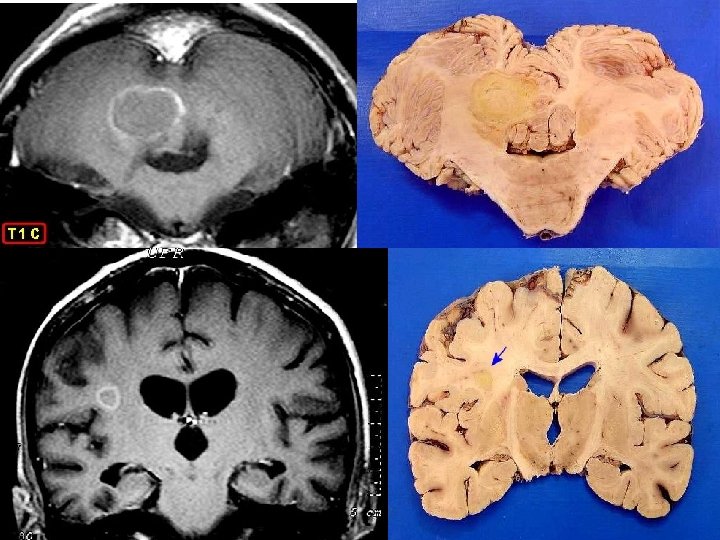

MACROSCOPIA DO CÉREBRO

RM T 1 corte axial de cerebro

RM T 2: hipersinal nos ventrículos

RM T 1 COM CONTRASTE Lesão anelar da neurotoxo não tem capsula

Toxoplasmose no SNC em pacientes imunocomprometidos: Sinais e sintomas de toxo aguda envolvem principlamente o SNC; Encefalite necrosante é causada por invasão direta do parasito; Necrópsia destes pacientes têm demonstrado o acometimento em múltiplos órgãos, e não apenas no SNC; Cometimento do SNC na toxo se dá no parênquima cerebral e não nas meninges;